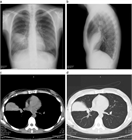

1. 無気肺とは肺組織が虚脱し、肺の含気が低下した状態である。

1. 閉塞性無気肺(腫瘍、粘液栓、異物、気管支結核など)と非閉塞性無気肺(炎症などによる肺実質の虚脱、受動性無気肺、円形無気肺など)に大別される。

1. 胸部X線撮影で無気肺が疑われたら、まずは胸部造影CTで鑑別をすすめ、必要に応じ喀痰培養、喀痰細胞診、気管支鏡などを行う。